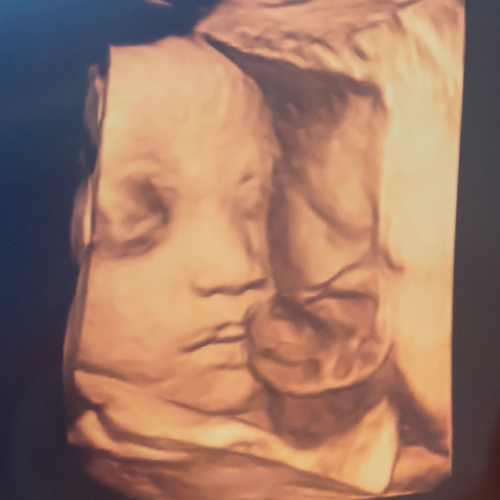

임신 테스트기에 선명한 두 줄이 나타났다.

‘바다(태명)’는 자라고 있었다.